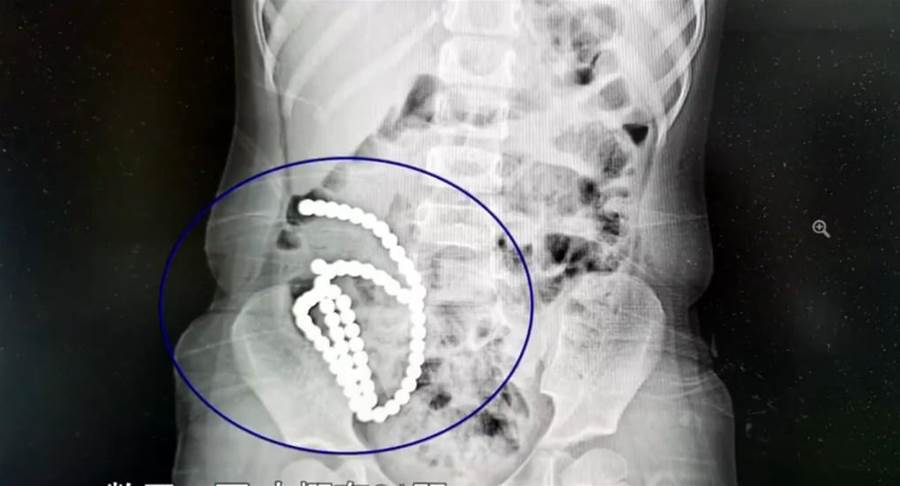

家有幼兒一定要特別小心照顧,如有不慎恐怕後悔一輩子也來不及。中國浙江大學醫學院附屬兒童醫院的急診來了一位小病患,4歲小妹妹肚子痛一個月以為是腸胃炎,直到轉院檢查照X光才發現「肚子裡有一串珠珠」。雖然緊急開刀治療,未來罹患後遺癥的風險卻相當高。

根據中媒《人民網》報導,院方發現4歲女童肚子裡有像手飾一般的串珠後,懷疑是誤吞磁力很強的「巴克球」磁力珠。問診後女童媽媽也透露家裡有這種玩具,平常是孩子的哥哥在玩。

經過將近2小時的手術,醫師將多達61顆磁力珠從女童的腸胃裡取出。

副院長兼腔鏡中心主任高志剛醫師表示,女童並非一下子把磁力珠通通吞下肚,而是分次慢慢誤食。前後吞下去的珠子因為磁力相吸,「2顆巴克球之間就會有腸管壁夾在中間,慢慢腸子就穿孔了」。高醫師說明把磁力珠取出後,女童的腸壁破了14個洞,雖然手術成功修補,但仍對健康造成極大的損害,「一輩子腸沾黏、腸梗阻的風險都很大」。